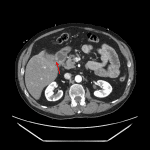

- 2.3 cm peripherally calcified structure likely representing a gallstone in the mid small bowel with upstream small bowel dilation, mural thickening, and submucosal edema

- Gallbladder is collapsed with wall thickening, intraluminal gas, and demonstration of a fistulous connection to the adjacent duodenum

- Trace pneumobilia

- Inflammatory fat stranding about the above described loops of small bowel as well as surrounding the gallbladder

- Gallstone ileus

Findings are consistent with gallstone ileus. A 2.3 cm peripherally-calcified gallstone is identified in the mid small bowel with associated upstream small bowel dilation and inflammatory changes. Superimposed ischemia is not excluded, though there is no convincing pneumatosis or portal venous gas.

Decompressed gallbladder with associated inflammatory changes and demonstration of a cholecystoduodenal fistula.